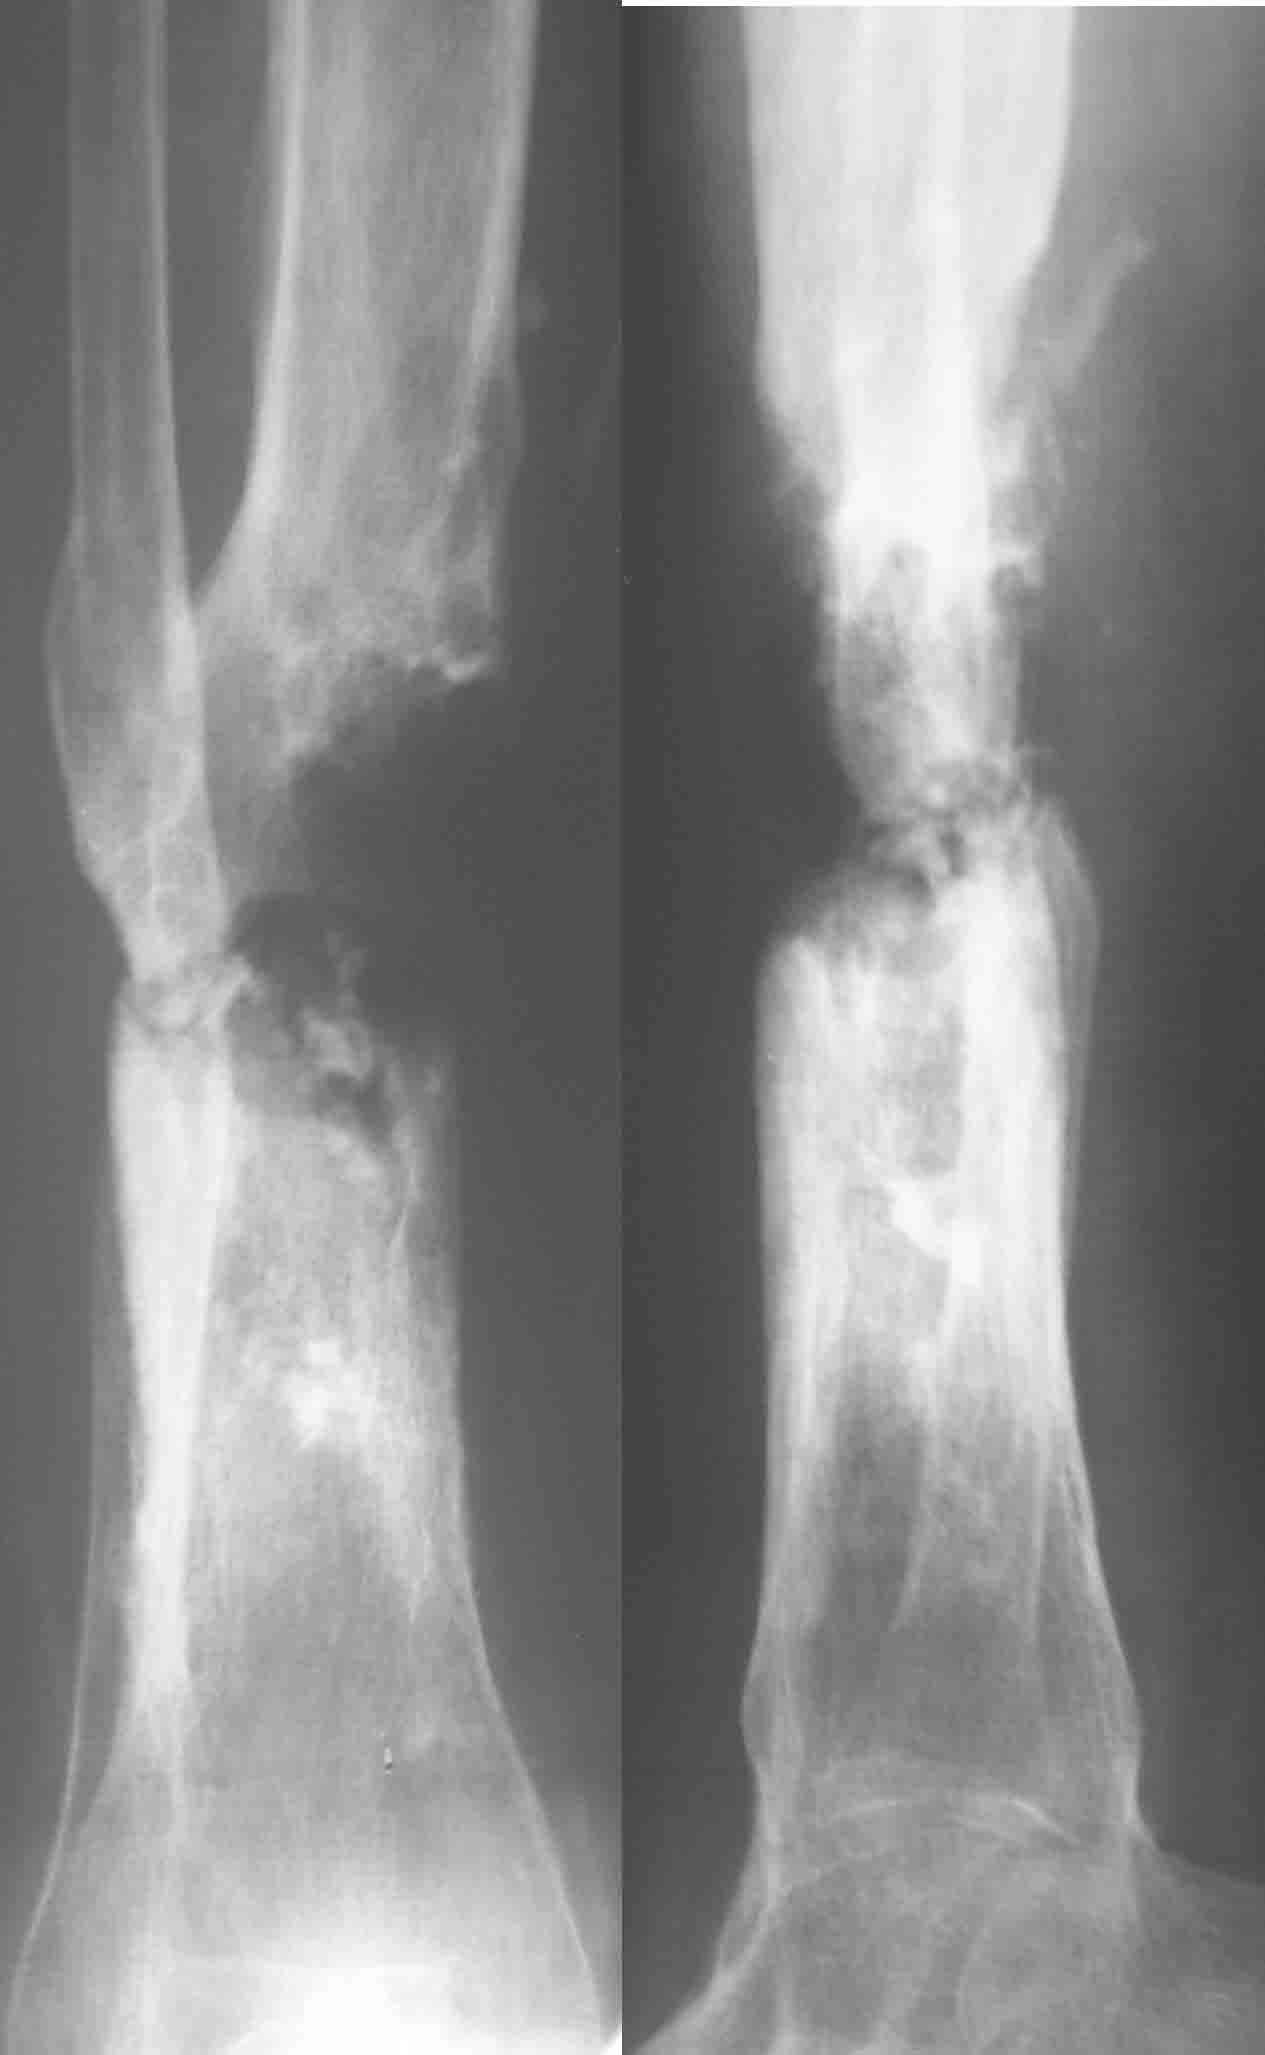

Позволю высказать свое мнение. У меня есть сомнения, что задняя стенка большеберцовой кости осталась "здоровой". Если после первой операции костная ткань и могла остаться частично жизнеспособной, то развившаяся гнойная инфекция наверняка способствовала окончательному некрозу кости.

Я бы, наверное, после удаления штифта сосредоточился на определения жизнеспособности кости по задней поверхности. Если будут сомнения, то я бы сделал резекцию.

Тогда можно рассмотреть вопрос одновременного удаления штифта, мышечной (в данной области применим проксимально отсеченный лоскут камбаловидной мышцы) или микрохирургической (что более надежно) пластики дефекта мягких тканей, остеотомии проксимального фрагмента большеберцовой кости, остеосинтеза блокируемым штифтом с а/б покрытием, наложения простого аппарата Илизарова (можно из полуколец) для дистракции на штифте. При данном варианте пациент сохраняет возможность полной опоры на ногу, что очень важно для заживления у пожилого пациента) и отпадает необходимость в проведении дополнительный операций (при благоприятном развитии событий).

Повторяю, что все это я бы затевал, при сомнениях в жизнеспособности кости.

Выкладываю картинки похожей пациентки. Извините, что без окончательных снимков (сейчас их нет под рукой). Правда мы имели проблемы у данной больной после снятия аппарата, когда промежуточный фрагмент большеберцовой кости сместился на 1,5 см дистально и отошел от проксимальной части кости. До сих пор у пациентки на снимках определяется лишь тонкая полоска кости по задней поверхности за штифтом (образовалось что-то вроде маленького регенерата)в области стыковки промежуточного и проксимального фрагментов. Больная пока решила подождать. Не хочет оперироваться, так как ходит не хромая, работает.